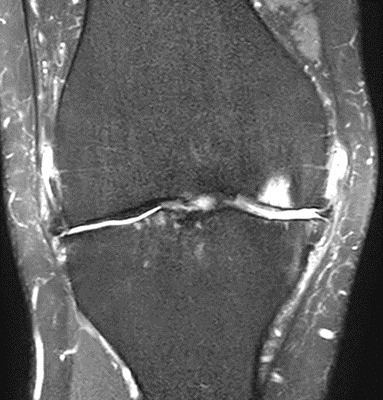

MRI scans illustrating the improvements regarding Group 2 are presented below, showing pre-treatment images with evident cartilage defects, pronounced bone marrow edema, and synovial inflammation, followed by post-treatment scans demonstrating improved joint structure, reduced edema, and decreased inflammation (Figures 12-29).

MRIs of Group 2

MRIs of Group 1

To provide a comparative perspective, additional MRI scans from Group 1 are shown subsequently. While patients in this group also displayed reductions in bone marrow edema, effusion, and synovitis, the improvements appeared less pronounced than those seen with the combined therapy. Pre-treatment MRI scans revealed extensive edema and synovial inflammation, which were partially reduced at the 2-month follow-up. However, residual joint effusion and subtle signs of inflammation remained present in some cases. These findings further support the potential benefit of combining the ChondroFiller® liquid with MSC therapy to achieve more comprehensive structural improvements and facilitate enhanced cartilage regeneration (Figures 30-41).